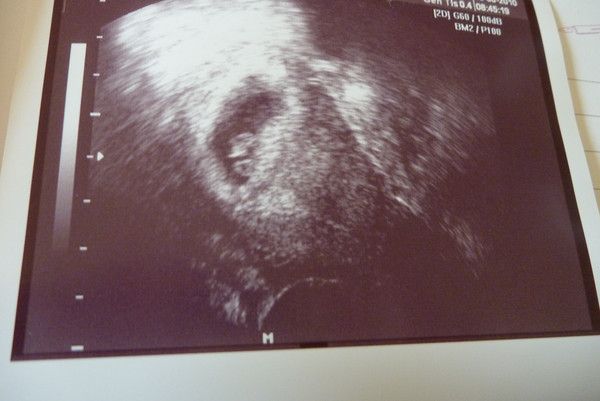

1.US_samulu_ET01042010

25.08.2010

zusehen ist schön der Embryo SSL 18mm; Markierung + ist Herzchen; rechts unten Nabelschnur und noch Dottersack

daraus ergibt sich eine Summe von ALLES OK in der 9.SSW (SSW8+5T)